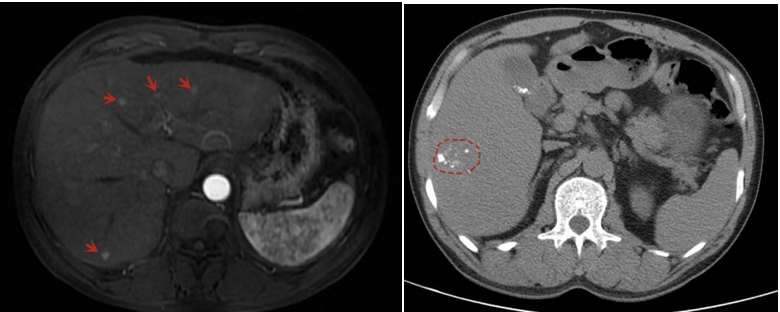

2020年3月5日行第1次cTACE,术中造影示肝动脉造影,多发肿瘤染色;化疗栓塞后复查,肿瘤染色消失(图2)。

图2.2020年3月15日TACE术中与术后造影

2020年4月14日,术后1个月复查上腹部CE-MRI,肝内多发异常信号影,较术前略缩小,增强可见动脉强化,门静脉未见充盈缺损;CT示:肝内多发低密度影,碘油部分沉积(图3)。2020年4月15日AFP:39.91ng/mL。

图3.2020年4月14日上腹部CE-MRI/CT

2020年6月17日,术后3个月上腹部CE-MRI/CT示,肝内原有病灶控制尚可,有新发病灶,增强可见动脉强化,门静脉未见充盈缺损。CT:肝内多发低密度影,碘油部分沉积(图4)。2020年6月15日AFP:115.60ng/mL。

图4.2020年6月17日上腹部CE-MRI/CT